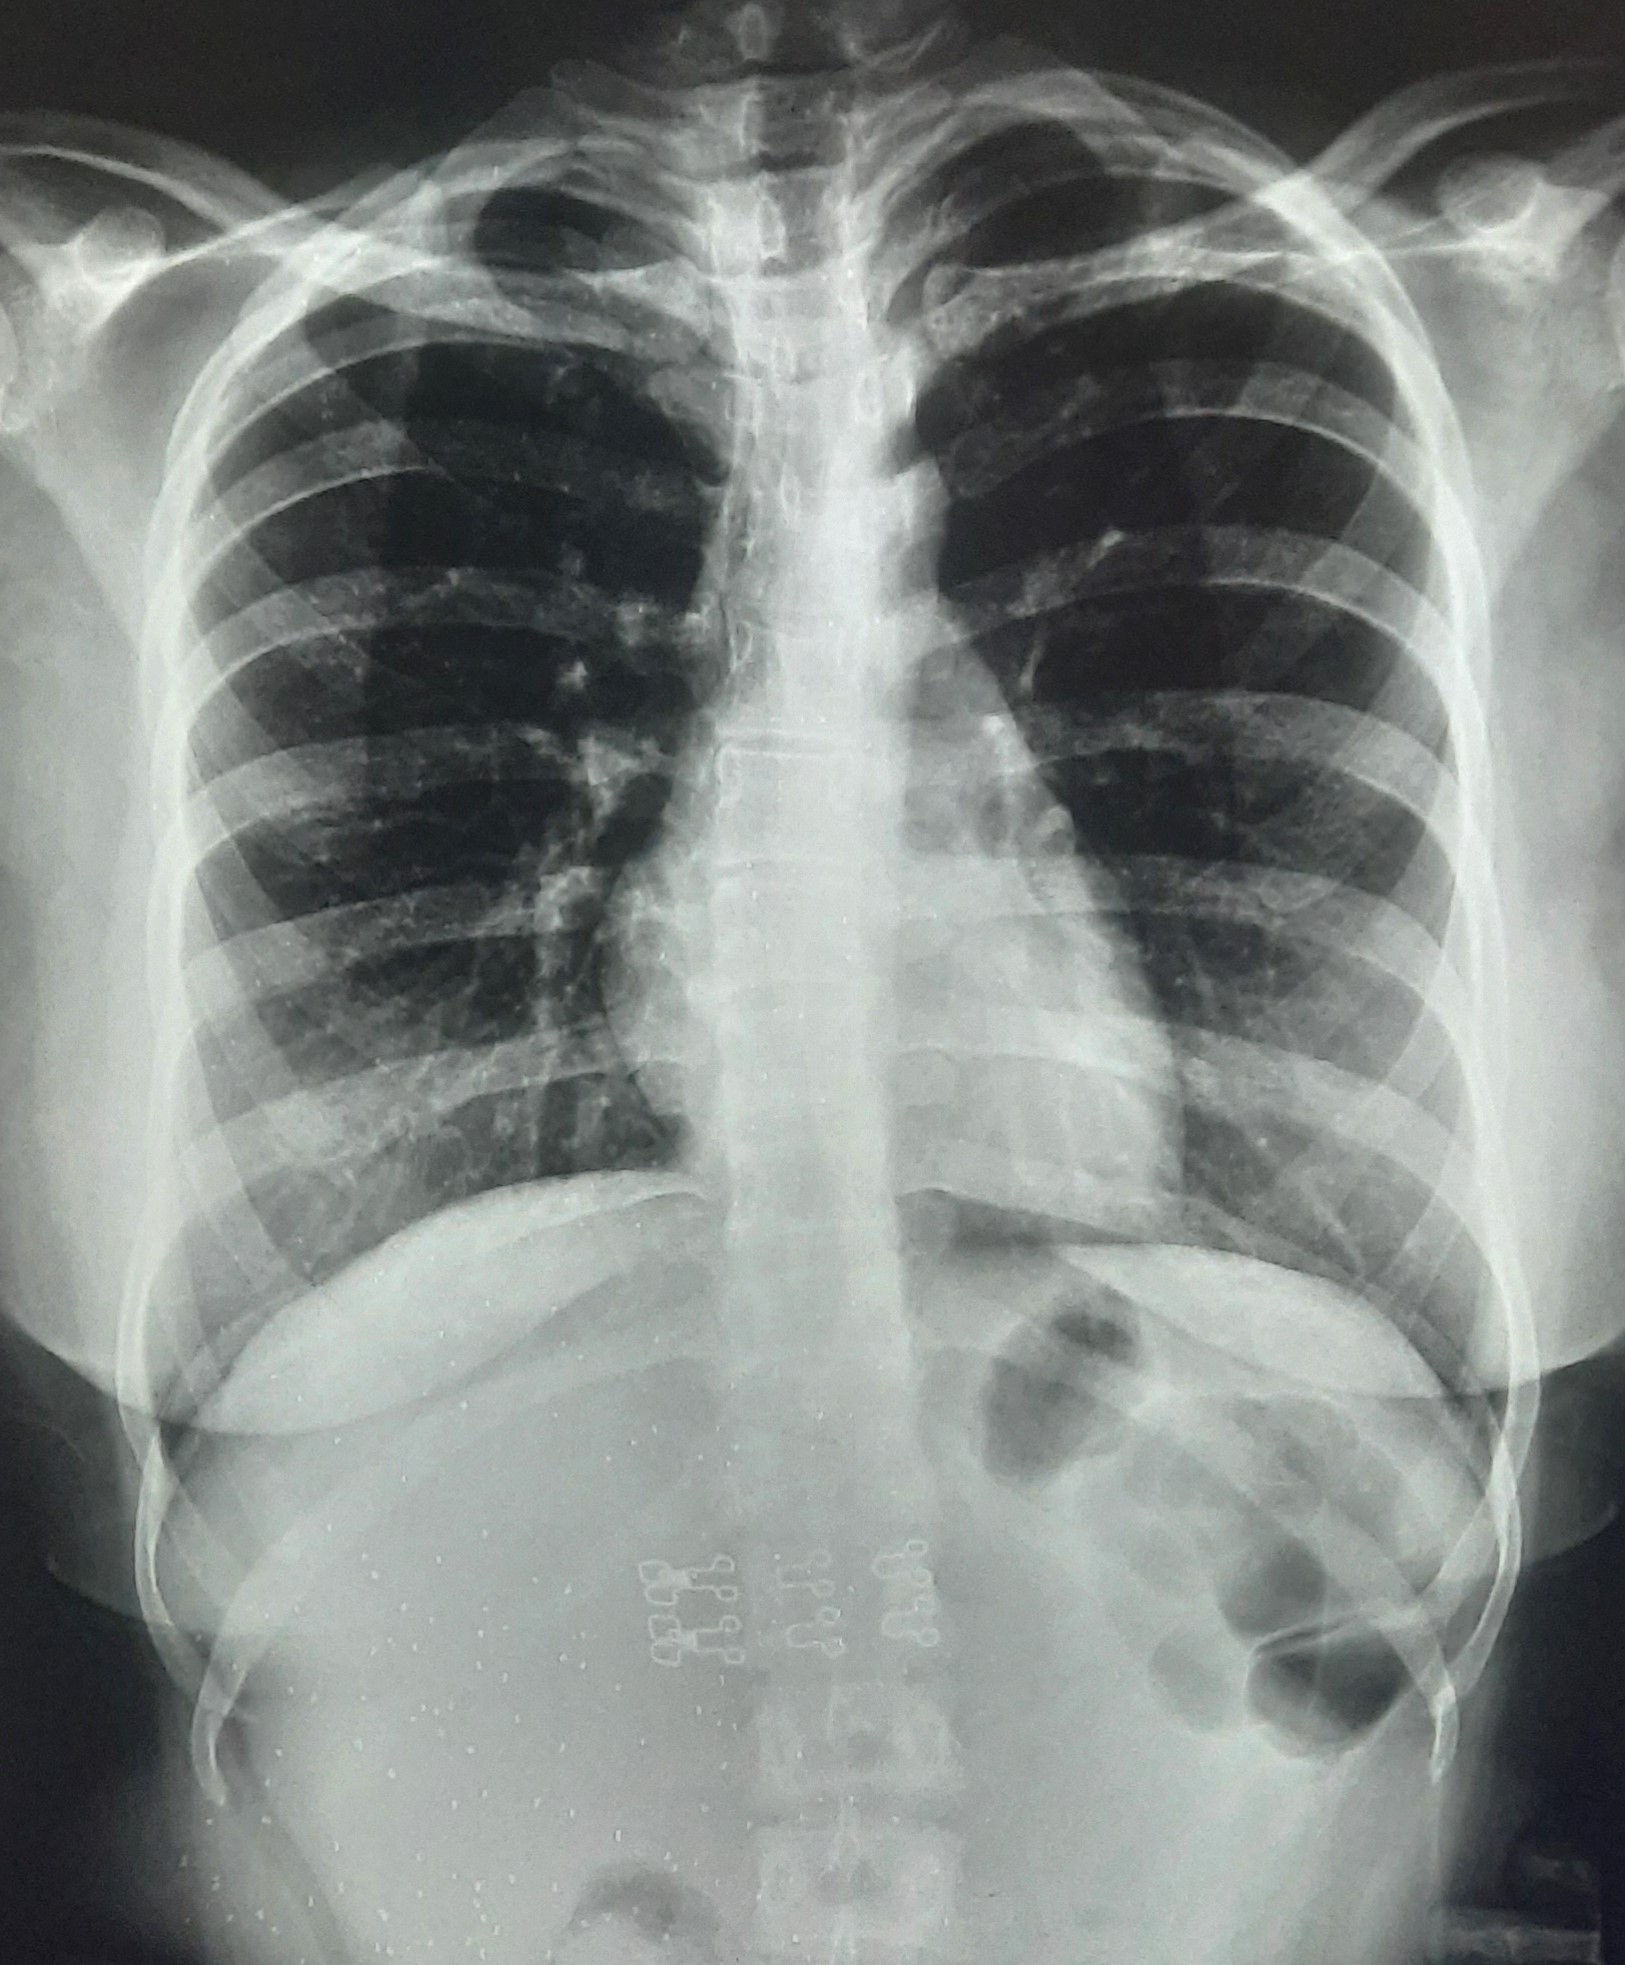

| 295 | IGGMC, Nagpur, Nagpur | P2 | 29-4177 | Afra Firdos | Consent taken on Paper | 14 Yrs. |

Provisional Diag : Pleural Effusion ?

Final Diag : Pleural Effusion |

Result awaited (Suspected TB/Non-TB) | Right Sided Pleural Effusion | Abnormality visible on x-ray |